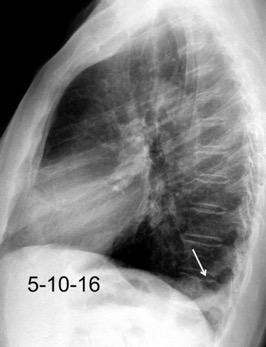

25. DERRAME PLEURAL. TRAUMA

26. DERRAME PLEURAL UNILATERAL. ENF. SUBDIAFRAGMÁTICA

27. DERRAME PLEURAL IZQUIERDO. URINOMA

28.DERRAME PLEURAL IZQUIERDO. PANCREATITIS AGUDA

29. DERRAME PLEURAL IZQUIERDO. SÍND. DE AFECTACIÓN POSTCARDIACA

30. DERRAME IZQUIERDO. SÍNDROME DE BOERHAAVE